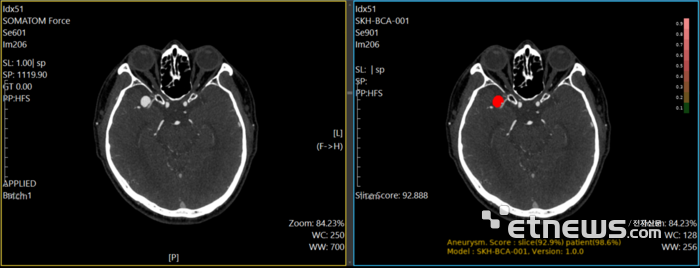

- AI 통합형 원격협진 플랫폼...의료취약지 뇌출혈환자 지켰다

현재 ![]() 퍼플에이아이 한국∙중소기업 | ![]() 퍼플에이아이 인공지능기반 뇌질환 진단 솔루션 | 인공지능 | 바이오/의료 뇌질환 | Pre-A 알 수 없음 |